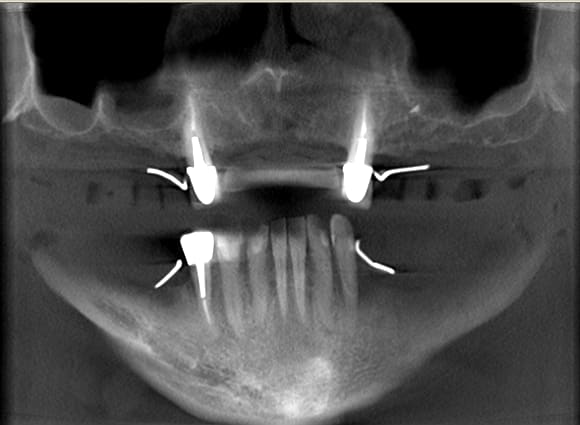

Au maxillaire il faut faire une implanto totale et stt ne pas garder les canines

A la mandibule faut disker mais ça va

PS il faut d abord faire réaliser des modèles stéréolithographiques par Materialise pour se prononcer au final

Mais c est un joli cas ;-)))))))))

Je suppose que le patient a porté de magnifiques stellites...

Cas promis... à dentiste 57 et à growler... le voici

L'axe de certains implants semble un peu trop palatin, mais bon, il n'y a pas de nonos...

2. Effectivemeznt les plaques zygomatiques ont des émergences palatines mais au définitif j ai ôté les piliers prlongateurs de 3.5 mm et du coup même si sortie palatine plus aucun "débordement" du puits de vissage en dehors de l arcade...

De tte façon si tu fais pas ce que je viens de faire, tu es cuit pour deux sinus-lifts ( dont la patiente ne voulait pas !!!!! )et encore tu n auras aucun implant au delà des 4 voire des 3 donc un terrible porte-à-faux devant... Sinon tu dois ajouter un Lefort pour interposer un bloc au niveau incisif... Elle refuse encore plus le Lefort que les sinus-lifts

PS Cette résorption est le résultat du port d un amovible complet de 30 ans à 63 ans ...

1. les palques ont une assisse énorme par rapport à 7 cylindres

2. la résorption centripède du maxillaire le rend trop petit pour en poser plus

De plus malgré le grand overjet , on a qd même un implant central qui soutient l arc incisif, même s il est 2 cm en arrière de la ligne des dents